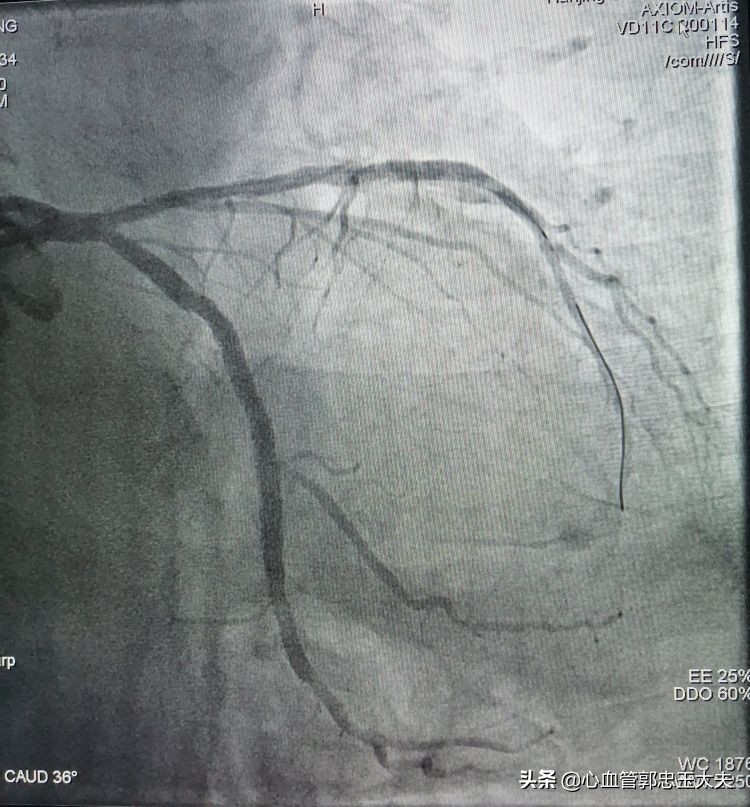

改变策略先在回旋支近段到远端植入支架2枚(如下图)

支架植入后,在回旋支再次预埋球囊,扩张后支撑力明显加强,微球囊通过闭塞病变,扩开闭塞血管。最后前降支植入支架,影像效果满意(如下图)

总结:该患者前降支中远段完全闭塞合并钙化,因此导丝通过病变非常困难,微球囊支撑后导丝过血管闭塞段,在回旋支预埋球囊扩张加强支撑,微球囊仍然难以通过闭塞病变。改变策略在回旋支植入支架后再次预埋球囊,支撑力明显加强,微球囊通过闭塞病变,扩张开病变血管,支架得以植入。